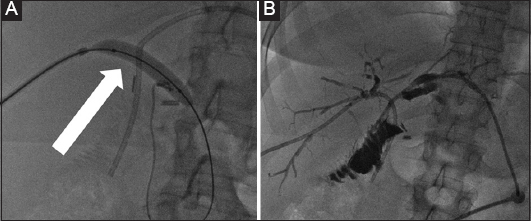

Figure 2 A 45-year-old female patient who developed benign biliary stenosis post laparoscopic cholecystectomy, with presence of stones. (A) Bilateral biliary drainage and dilation of the stenotic anastomosis with a high-pressure balloon (arrow). (B) Long-term drains with discoid end were left in situ for several months and the patient returned every 3 weeks for sequential dilation

Figure 3 A 48-year-old female patient with benign stenosis post biliodigestive anastomosis. (A) Initial drainage because of multiple small stones. (B) Cholangioscopic inspection to assess the presence of stones that were not visible in the cholangiogram. (C) Three months later, a new cholangiogram revealed the presence of a large stone (arrow). (D) The stone was retrieved with an extraction balloon. Presence of a “buddy-wire” to maintain access to the biliary tree